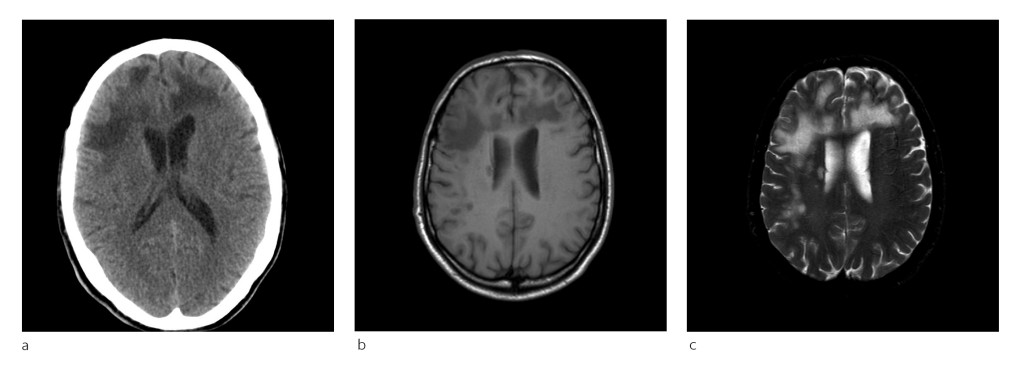

Patient 1. A man in his sixties with known chronic lymphocytic leukaemia was hospitalised owing to loss of strength in his left arm, cognitive difficulties and problems with everyday tasks. Upon clinical examination, he appeared to show psychomotor retardation and had difficulty cooperating with testing. A mild spastic left-sided hemiparesis was noted.

CT and MRI scans were performed (Fig. 1). A PCR assay for JCV DNA revealed large amounts of the virus in the cerebrospinal fluid: 4.1 billion copies/ml. The cerebrospinal fluid was otherwise normal. Human immunoglobulin was administered intravenously (Octagam), but the patient gradually deteriorated and died in hospital a few weeks later.

Figure 1 a) In patient 1, CT of the head showed bilateral non-specific confluent hypointensities in frontal subcortical…

Figure 1 a) In patient 1, CT of the head showed bilateral non-specific confluent hypointensities in frontal subcortical regions. B) T1-weighted MRI series revealed multiple areas with low signal, as in FLAIR series and c) T2-weighted series showed high signal. There was no sign of mass effect and the lesions were not contrast-enhancing.

MRI must be performed upon suspicion of progressive multifocal leukoencephalopathy. Changes may be observed in the cerebral white matter in the form of multiple small lesions and/or larger confluent areas anywhere in the cerebrum, most often subcortically (Fig. 1), as well as in the cerebellum and brainstem (Fig. 3). Signal intensity changes in the spinal cord should raise suspicion of an alternative diagnosis; these have been reported in progressive multifocal leukoencephalopathy, but only very rarely (20). Normal MR images usually rule out the condition, but MRI should be repeated in the event of ongoing clinical suspicion.